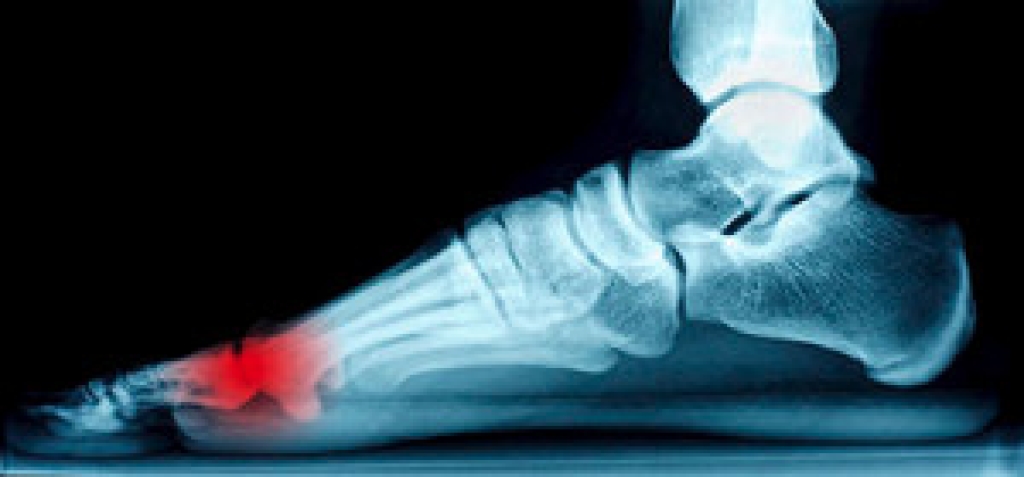

Cracked Heels

It is important to moisturize your cracked heels in order to prevent pain, bleeding, and infection. The reason cracked heels form is because the skin on the foot is too dry to support the immense pressure placed on them. When the foot expands, the dry skin on the foot begins to split.